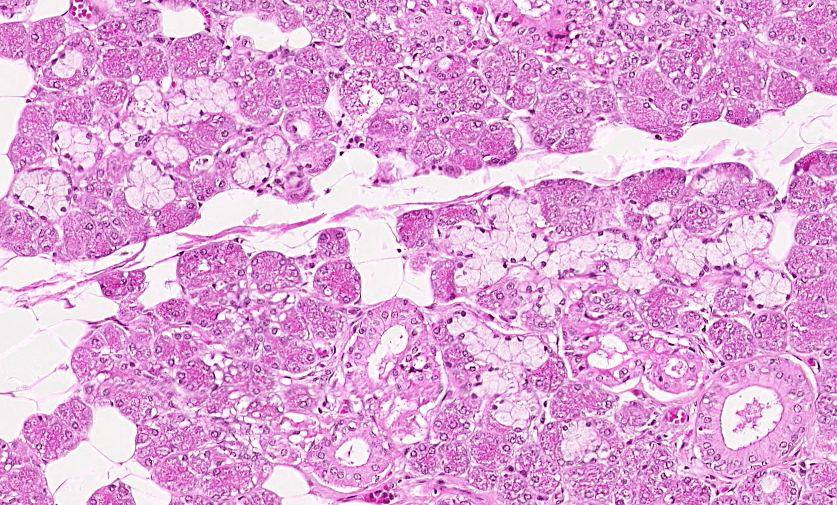

SUDORÍPARAS ECRINAS/MEROCRINAS

Ubicadas en toda la piel excepto labios y genitales.

NO asociadas a folículos pilosos.